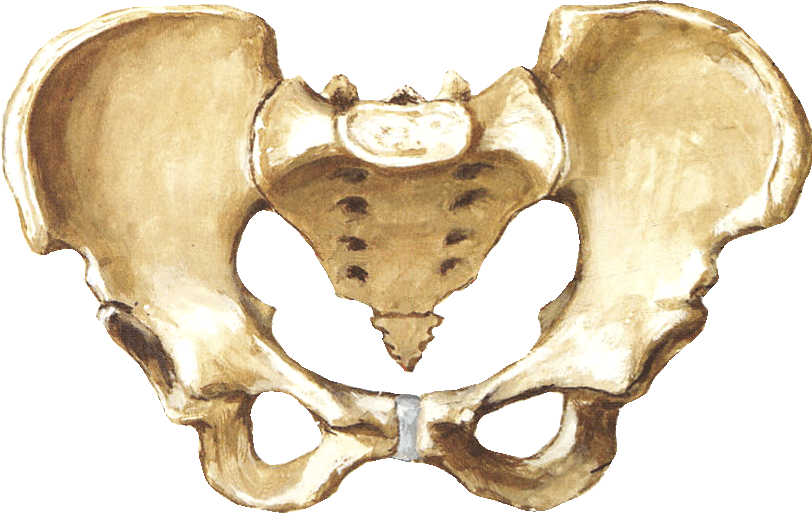

Анатомия малого таза: детальные схемы и изображения